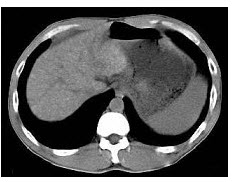

2、单项选择题

根据所提供的图像,最可能的诊断是()

A.胰腺癌

B.肝细胞瘤

C.胆管癌

D.胆囊癌

E.以上都不是